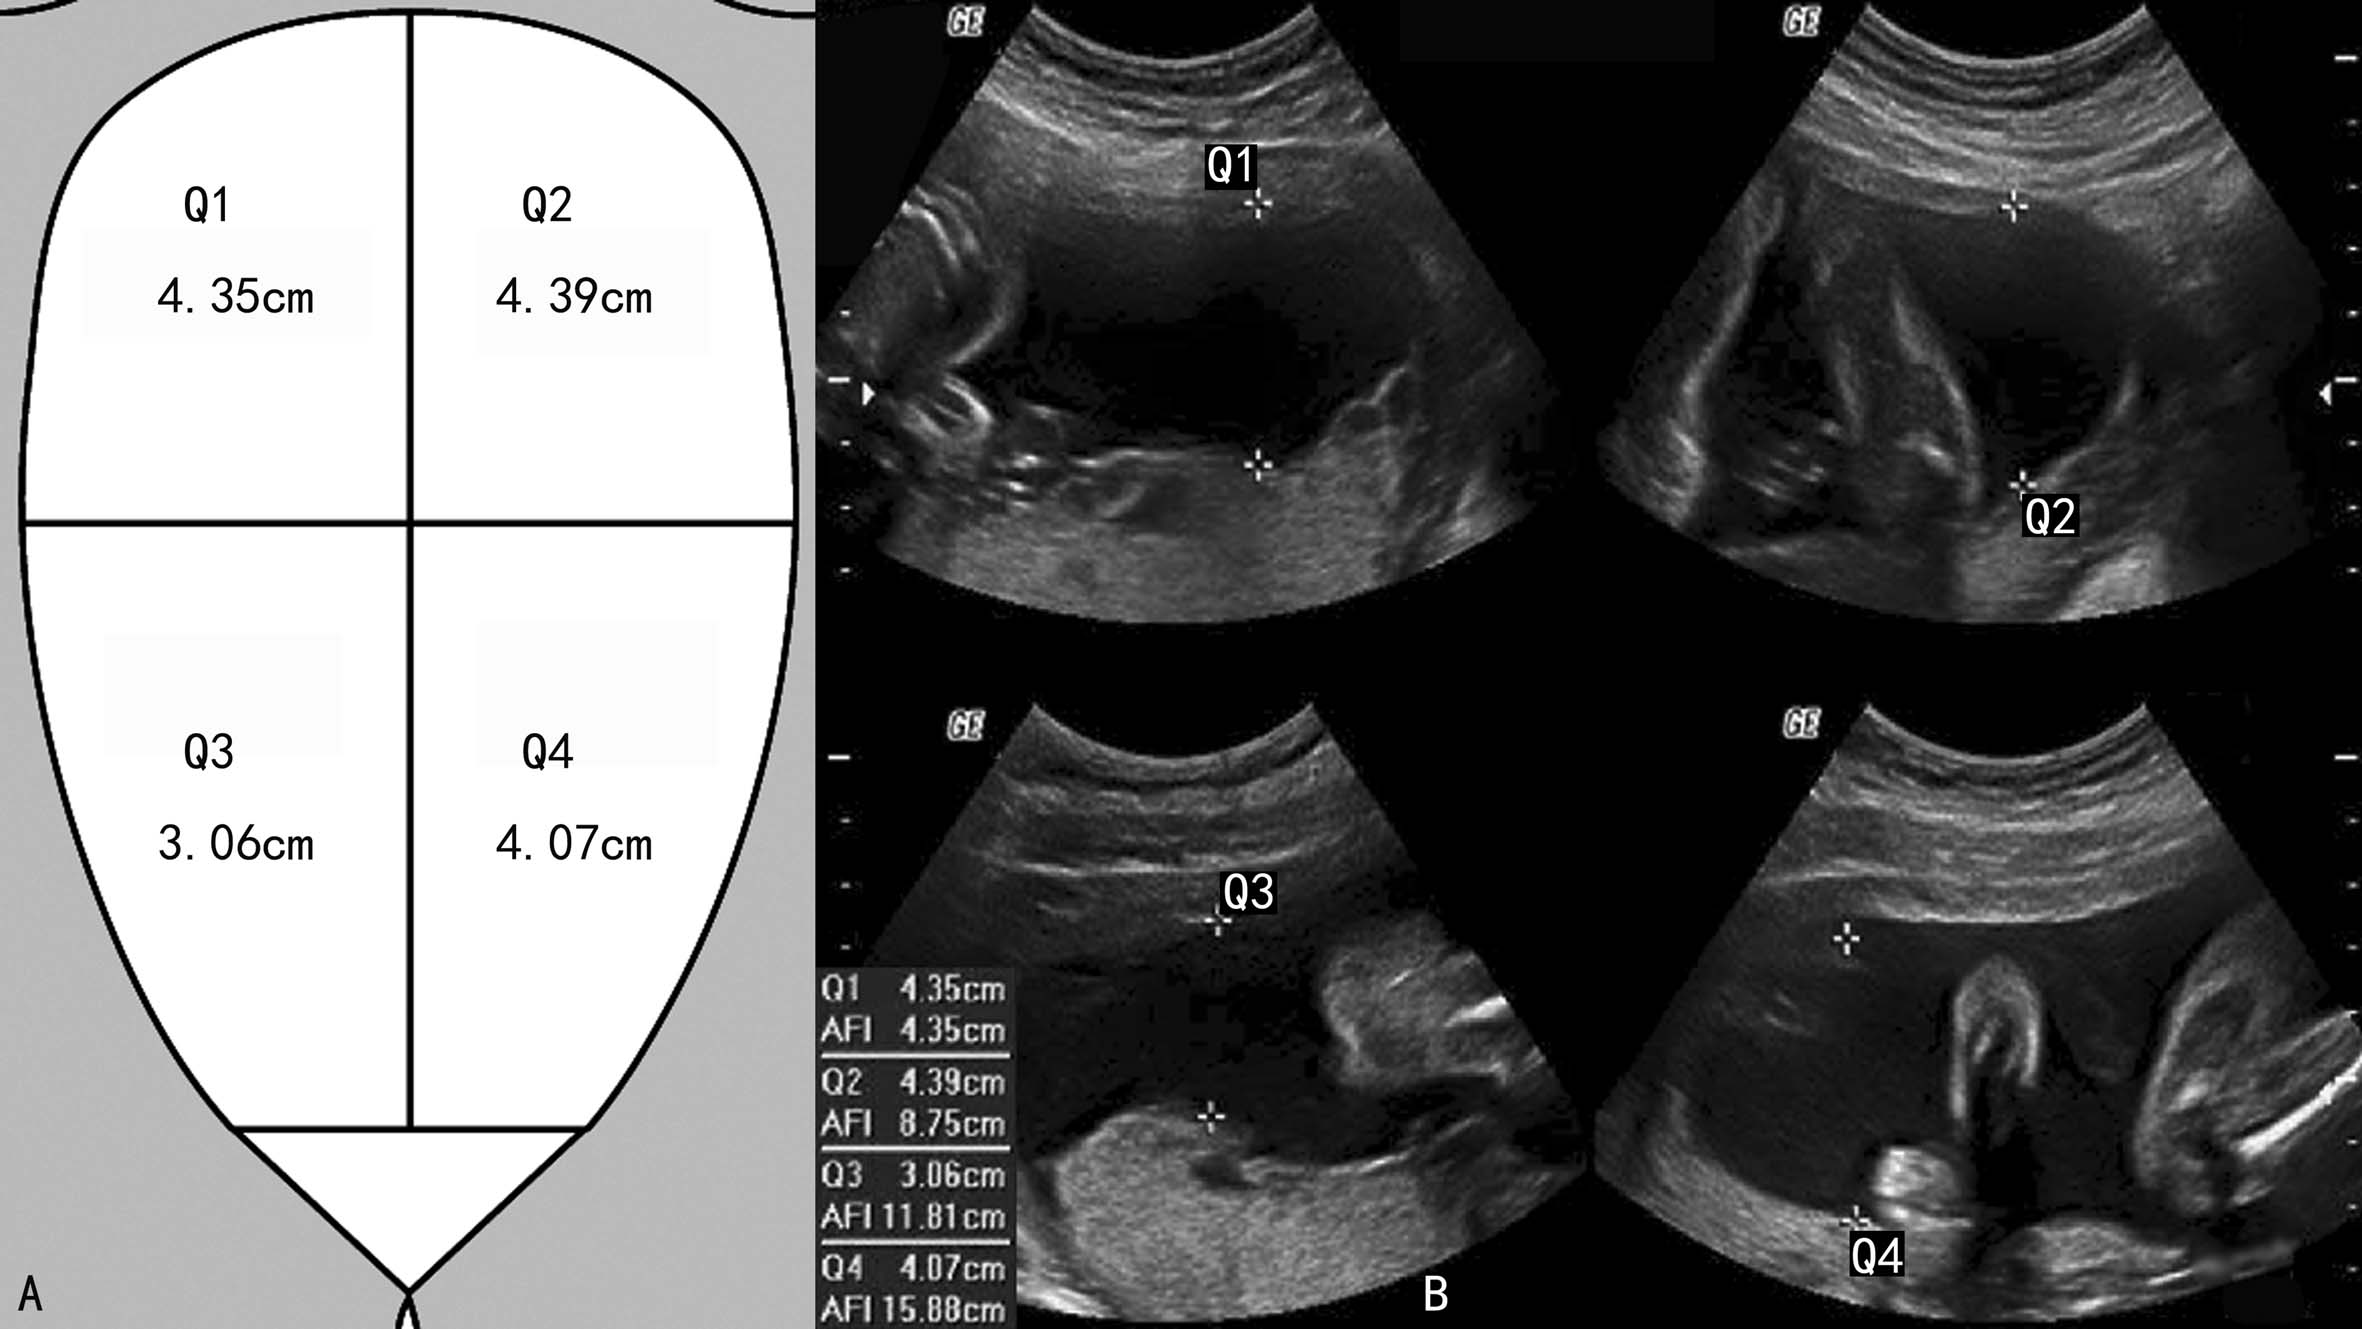

3.羊水指数法 将妊娠子宫的体表投影分为四个象限,测量四个象限内最清晰的羊水池内径,将测得的数值相加获得的和称为羊水指数(AFI) (图4)。测量时应当注意避开充满胎儿肢体或脐带的区域,但如果仅包含部分胎儿肢体或脐带则可以用做测量区。

图11-14羊水指数评估羊水量

正常时羊水指数为8~22cm。